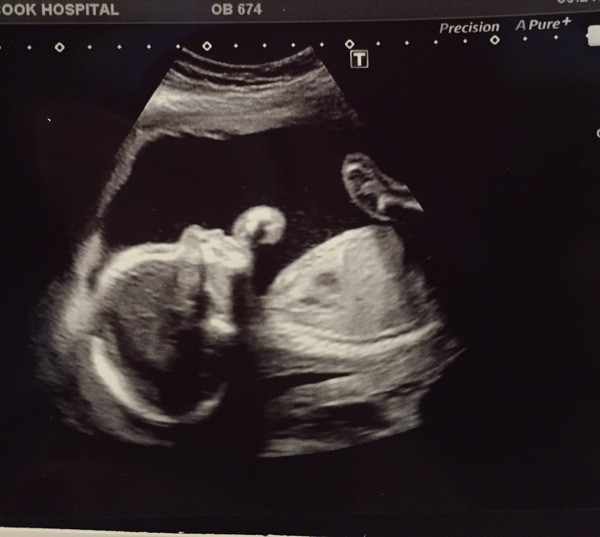

Hi, another good scan here. Baby in an awkward position so I had to go out and drink more water then go back in! Luckily she then managed to see everything. All was well, we are still team yellow, and I don't think the scan gives anything away! But feel free to guess!

Oh, I didn't attach the picture! Try again

OwlinaTree · 01/04/2016 20:13

Owlina I think your baby looks just like mine! I'd hazard a guess we're having the same (boy/girl) or we're long-lost relatives

21+4

Owlina and Zumba My little boy has the same headshape and profile on his ultrasound as yours Wink